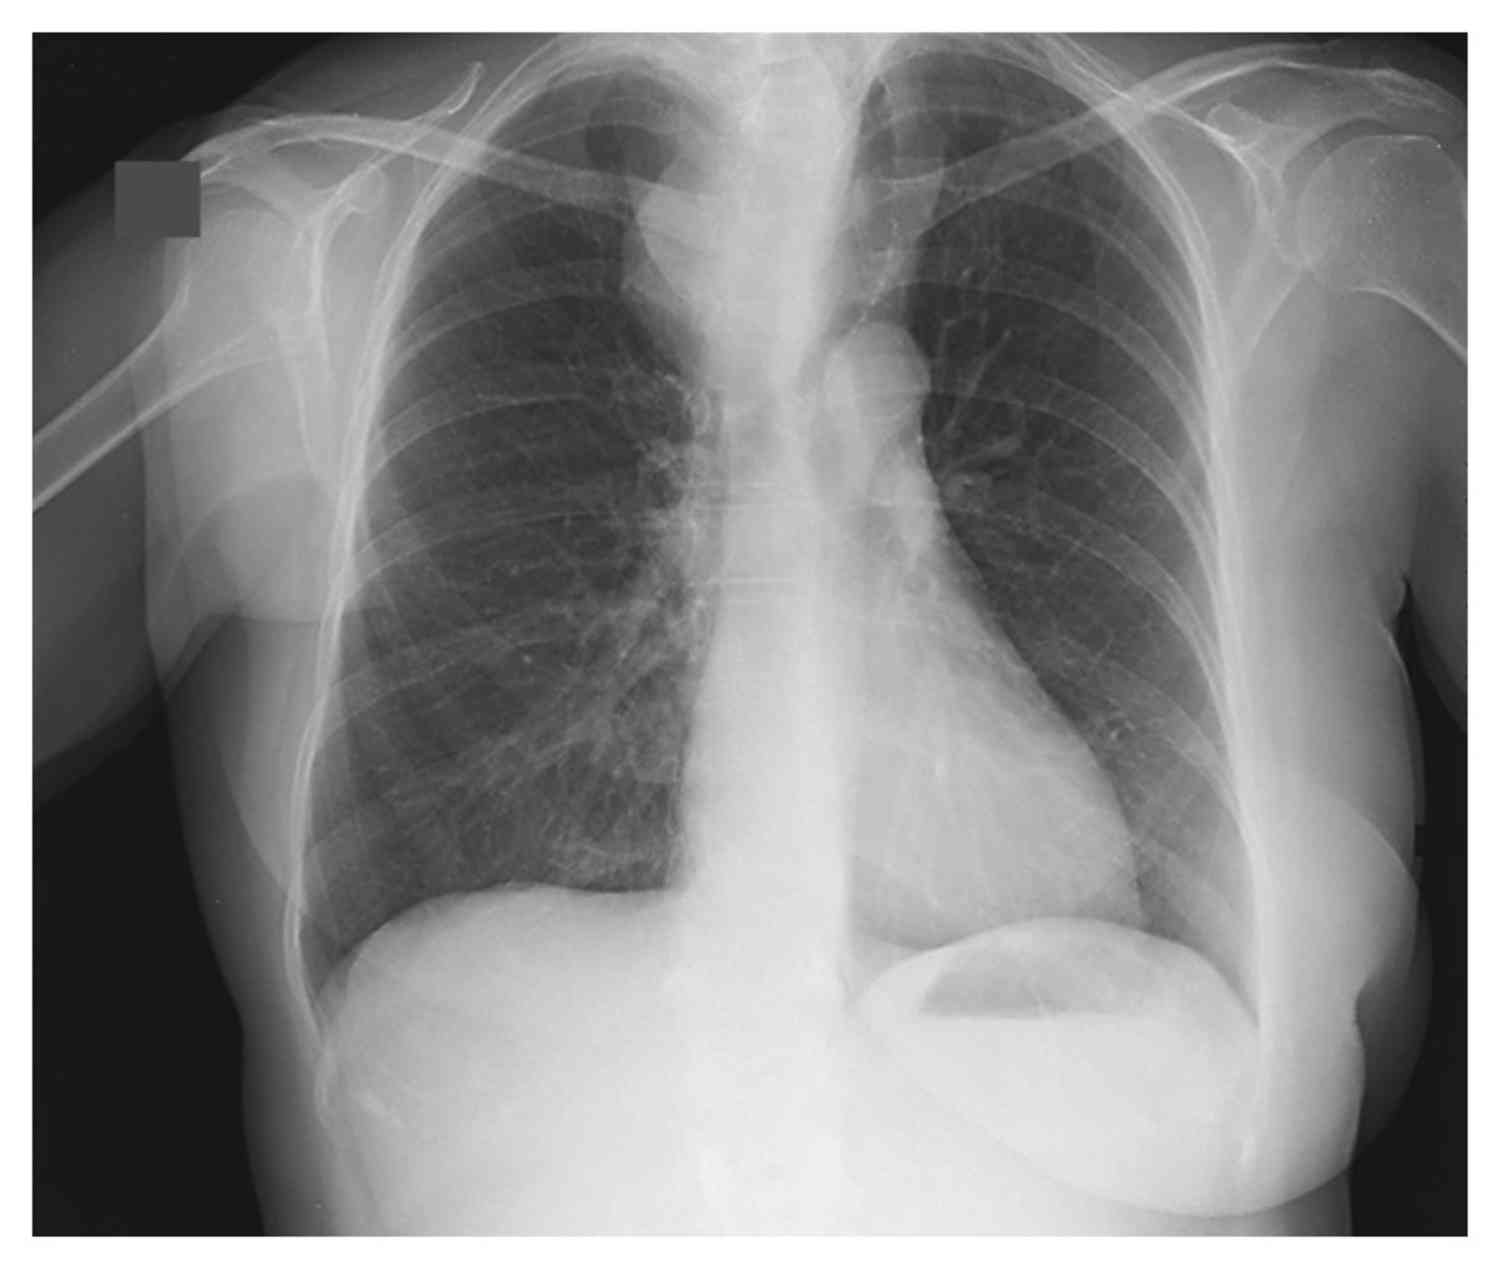

A 67-year-old woman presented with a 6-month history of dyspnea and dysphagia.

What is the diagnosis?